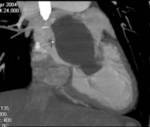

Results: Twenty-two cardiac masses were successfully detected and their characteristics adequately delineated, including eight myxomas, one angiosarcoma, one ventricular lymphoma, one endocardiac metastasis, one epicardiac paraganglioma, and 10 cases of intracardiac thrombi.

Conclusion: CT and MRI are noninvasive imaging modalities which can delineate cardiac tumors and masses and provide essential information for adequate diagnosis, staging and treatment planning. Compared to cardiac ultrasound, CT and MRI are superior in preoperative planning.